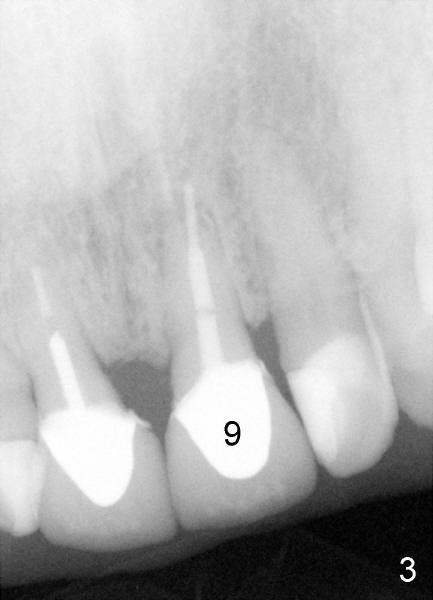

Sixty-five year old man is a bruxer, as shown in Fig.1, 2 (upper. lower arch, respectively, mirror view).  He has a night guard.  Fig.1-3 and Fig.4,5 are taken before and after crown fracture of the tooth #9, respectively.  It appears that the tooth is nonsalvageable.

Although gutta percha of #9 is overfilled, there is no active infection (Fig.3,4).  Can we place an implant immediately after extraction without loading or minimal loading?